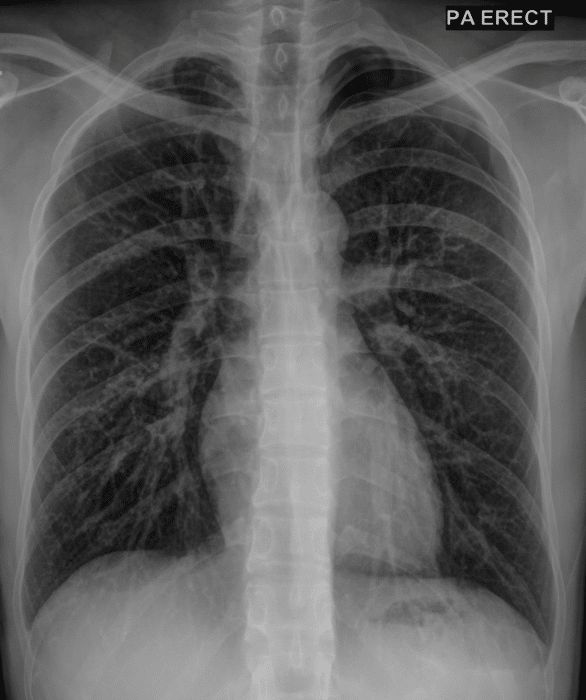

lung disease or infection

more pneumonia cases found compared to X-ray thanks to dual-energy images⁴

Lung Injury and Pulmonary Abnormalities